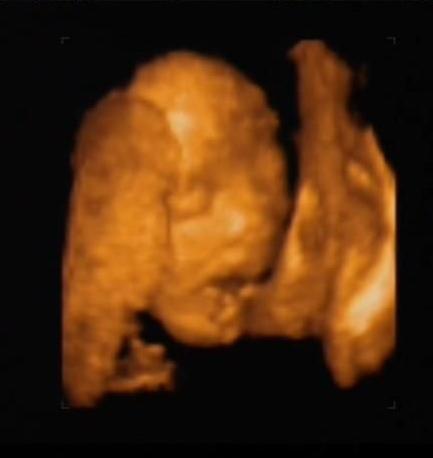

És (Titim rád gondoltam, még a könnyem is kijött) láttam a kicsi száját, az alsó-felső ajkát, mindenét...

Persze nehogy azt higyjétek, hogy élvezte a kukucskálást. Megmutatta a lényeget, de aztán elfordult, eltakarta magát... Nem is akárhogy!!!

A lábacskám...